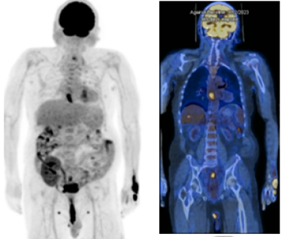

Postop histopathology of liver showing moderately differentiated hepatocellular carcinoma and Rectum showing moderately differentiated adenocarcinoma of rectum with free margins and free regional lymph nodes with perirectal tumor deposits pT3N1c. He received adjuvant external beam radiotherapy in view of T3 and node positive using Image guide radiotherapy (IGRT) to a dose of 45 Gy in 25 fractions to the post op bed and nodes in pelvis followed by 5.4 Gy in 3 fractions boost to the post-operative bed as shown in Figure 3 along with concurrent chemotherapy with oral capecitabine The patient received stereotactic body radiotherapy(SBRT) using CyberKnife to a dose of 30 Gy in 5 fractions to postop bed of liver using gold fiducial and synchrony respiratory tracking as shown in Figure 4. SBRT to liver considered in view of close margin 2mm.now on one and half year follow up whole body PET scan as shown in Figure 5 revealed no active disease and patient have a good quality of life.

Figure 5 Current whole Body PET CT.